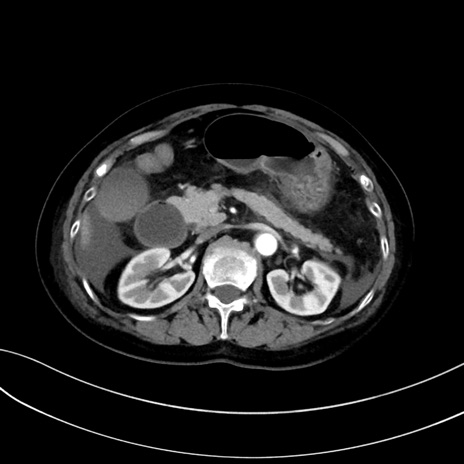

症例13 CT(横断像)1日半後